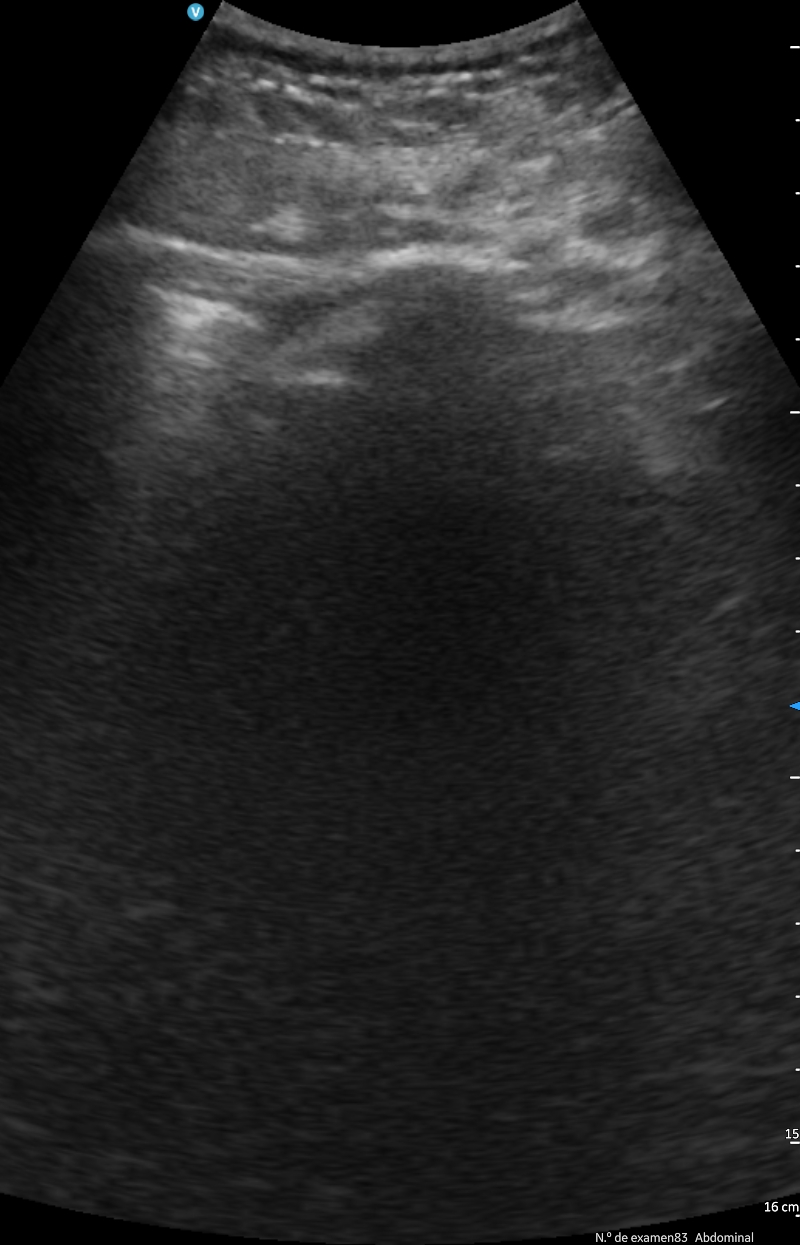

El principal uso ha sido para controlar la evolución de las insuficiencias cardíacas, controlando las líneas B, los derrames pleurales, colapso de la vena cava inferior, etc., en menores casos se ha hecho una ecocardioscopia para estimar la FEVI.

También ha sido útil en las insuficiencias respiratorias por COVID-19 o por neumonías para controlar las consolidaciones y los derrames pleurales.

Otros usos, aunque en menor medida, han sido control de ascitis, valorar retención de orina, valorar hidronefrosis, descartar trombosis venosas profundas y en pocas ocasiones control de abscesos o infecciones de partes blandas.